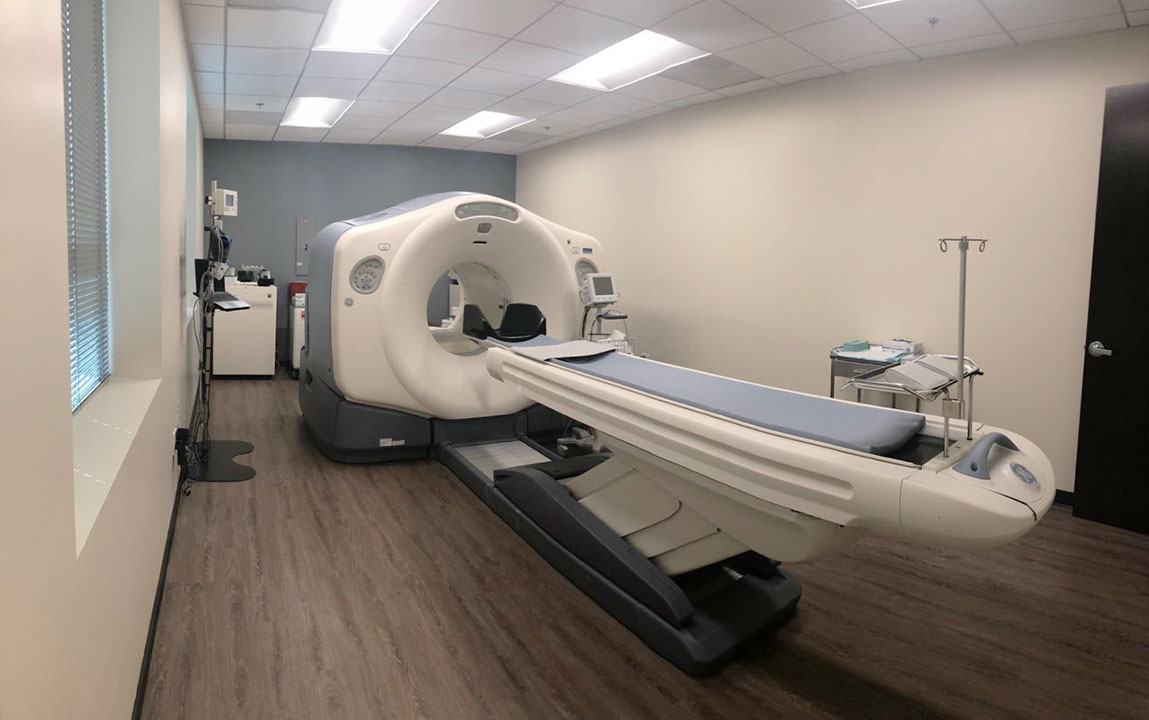

Enhance your business with our stunning commercial Cardiac Pet/ct collection of numerous professional images. optimized for commercial use with truck, vehicle, and automobile. ideal for corporate communications and branding. Discover high-resolution Cardiac Pet/ct images optimized for various applications. Suitable for various applications including web design, social media, personal projects, and digital content creation All Cardiac Pet/ct images are available in high resolution with professional-grade quality, optimized for both digital and print applications, and include comprehensive metadata for easy organization and usage. Discover the perfect Cardiac Pet/ct images to enhance your visual communication needs. Our Cardiac Pet/ct database continuously expands with fresh, relevant content from skilled photographers. Reliable customer support ensures smooth experience throughout the Cardiac Pet/ct selection process. Professional licensing options accommodate both commercial and educational usage requirements. Multiple resolution options ensure optimal performance across different platforms and applications. Regular updates keep the Cardiac Pet/ct collection current with contemporary trends and styles. Each image in our Cardiac Pet/ct gallery undergoes rigorous quality assessment before inclusion. Time-saving browsing features help users locate ideal Cardiac Pet/ct images quickly. The Cardiac Pet/ct archive serves professionals, educators, and creatives across diverse industries. Comprehensive tagging systems facilitate quick discovery of relevant Cardiac Pet/ct content.